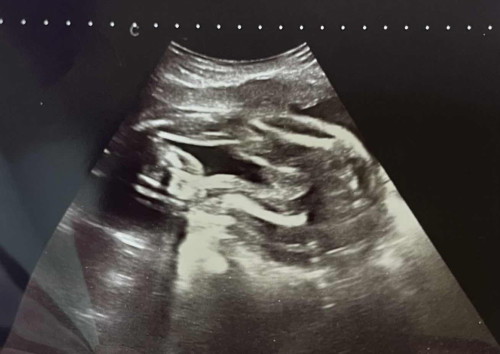

Baru2 ni scan gender masa 25w+ tapi doktor pun tak boleh pastikan sama ada baby boy or girl. Boleh ibu2 bagi pendapat tak baby saya boy or girl ye? #takkisahboyorgirl #firsttimemommy

Minggu lepas pergi buat detail scan jugak. Awal2 baby dah tunjuk pistol & doktor ada tunjuk pistol dia Nak tanya ibu2 dalam ni , ada kemungkinan ke kalau baby keluar nanti , dia jadi scam ibu dia sendiri kalau dalam detail scan dia dah belanja pistol dia?😅

Saya nampak mcm boy. Cuma dia kepit sikit tu yang tak nampak

Mcm boy sbb tk nmpak pulak 3 line burger sign